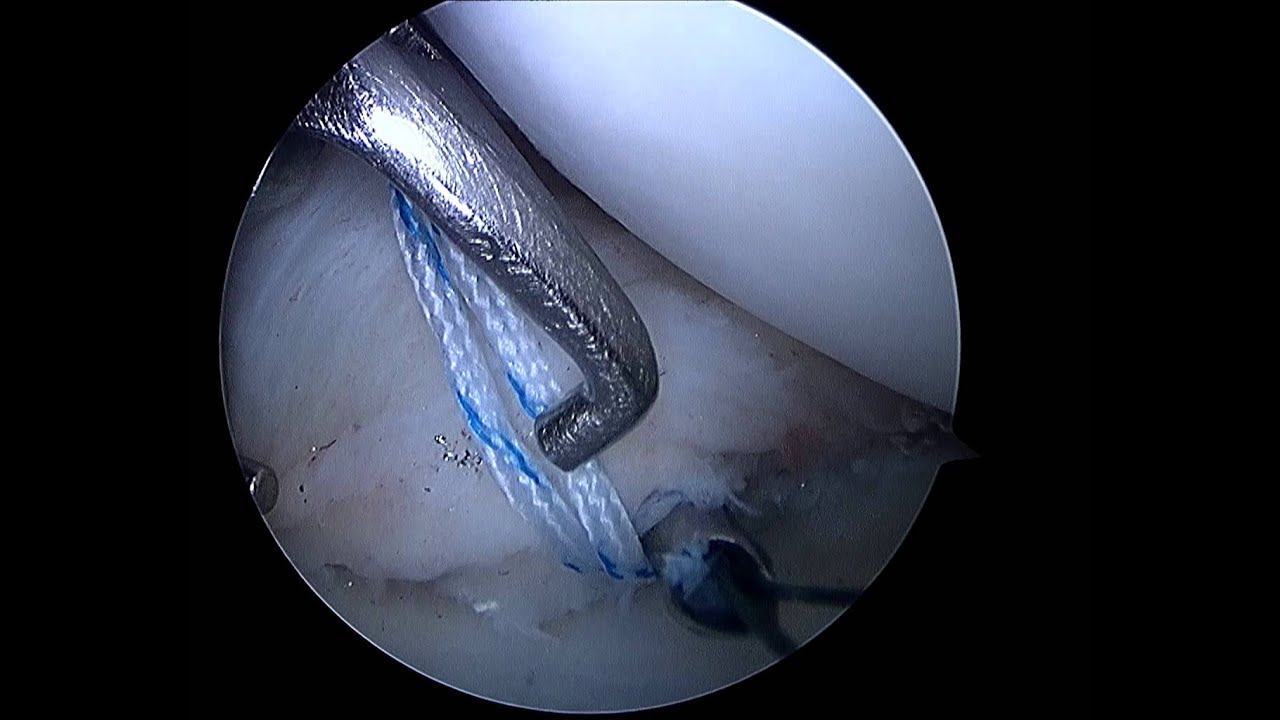

• Cirugía de menisco

Gran profesional!! Empatiza con el paciente; Se toma todo el tiempo necesario para explicar al detalle cualquier duda que se le plantee. Me inspiró mucha confianza desde el primer momento. Me operó del menisco interno y como nuevo!! Muchas gracias doctor!!

Muchísimas gracias por tus palabras y por la confianza que depositaste en mí desde el primer momento. Me alegra saber que te sentiste acompañado durante todo el proceso y que la intervención de menisco interno te ha permitido volver a encontrarte bien. Ese es siempre mi objetivo: explicar cada paso con claridad, tomar el tiempo necesario y ofrecer un tratamiento preciso y seguro para que cada paciente recupere su función lo antes posible.

Profesional fantástico, da explicaciones ilustradas con imágenes de las lesiones. Da buenos consejos para una pronta recuperación.

Muchas gracias por tu valoración y por destacar el valor de las explicaciones con apoyo de imágenes. Considero fundamental que cada paciente comprenda bien su lesión y el tratamiento propuesto, porque así la recuperación es más rápida y segura. Me alegra saber que los consejos te están ayudando en tu evolución. Seguimos a tu disposición en nuestra consulta de Traumatología y Cirugía Ortopédica en Granada para cualquier revisión o control que necesites.